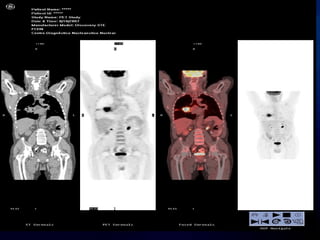

METODOS NO INVASIVOS –Factor N

METODOS INVASIVOS –Factor N